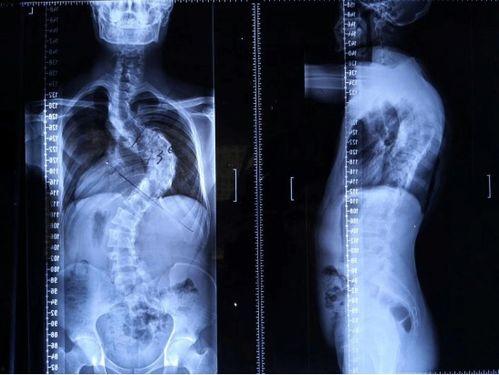

亲爱的读者,你是否曾因为自己不完美的身材而烦恼?尤其是那些脊柱弯曲的问题,是不是让你在镜子前黯然神伤?别担心,今天我要给你带来一个好消息——成人还能矫正脊柱!是的,你没听错,让我们一起揭开这个神秘的面纱,看看脊柱矫正的奥秘吧!

脊柱矫正,顾名思义,就是通过各种方法来调整脊柱的形态,使其恢复到正常状态。这个过程可能涉及到物理治疗、按摩、针灸、手术等多种手段。那么,成人还能矫正脊柱吗?答案是肯定的!

脊柱矫正的效果因人而异,但一般来说,经过一段时间的治疗,大部分患者的脊柱都会得到明显改善。具体效果如下:

1. 缓解疼痛:脊柱矫正可以缓解因脊柱弯曲引起的疼痛。

2. 改善姿势:脊柱矫正可以帮助改善不良的姿势,使身体更加挺拔。